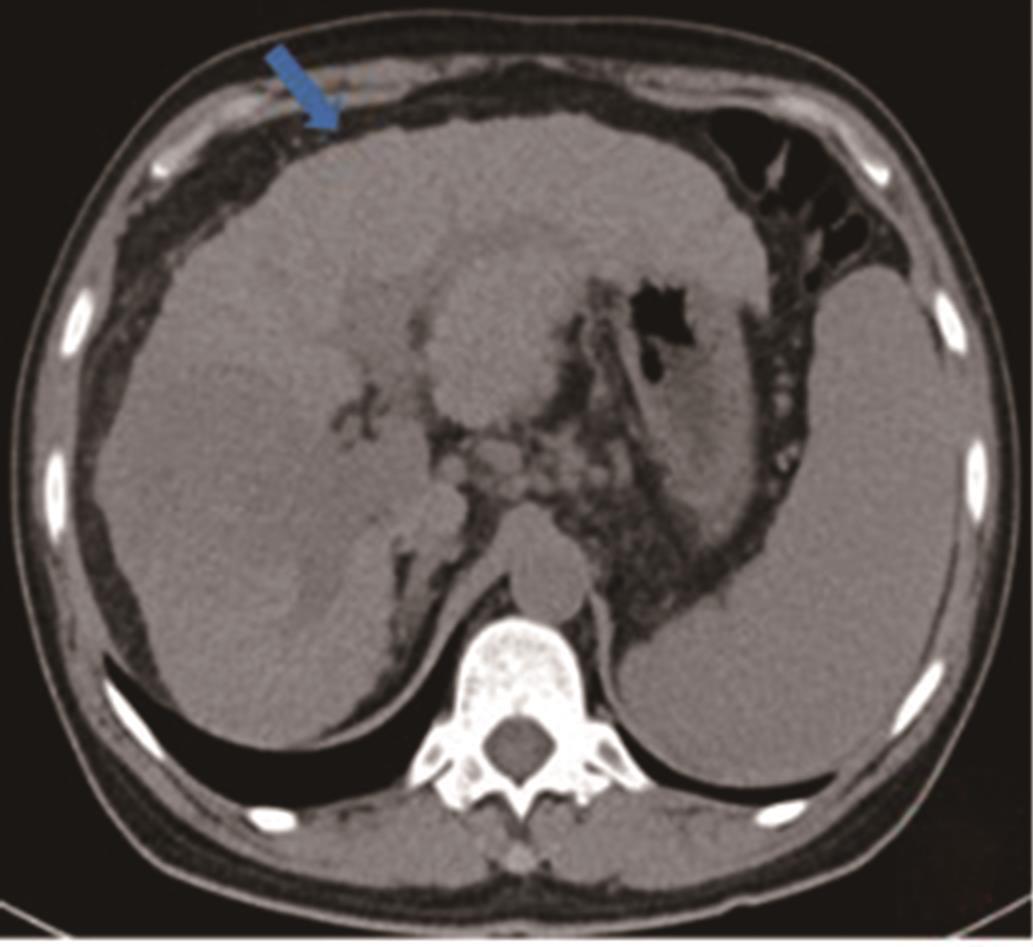

• 胆囊腺癌伴印戒细胞癌1例

2023, 48(3):366-368. DOI: 10.13406/j.cnki.cyxb.003035

摘要 (95) HTML (52) PDF 4.60 M (255) 评论 (0) 收藏